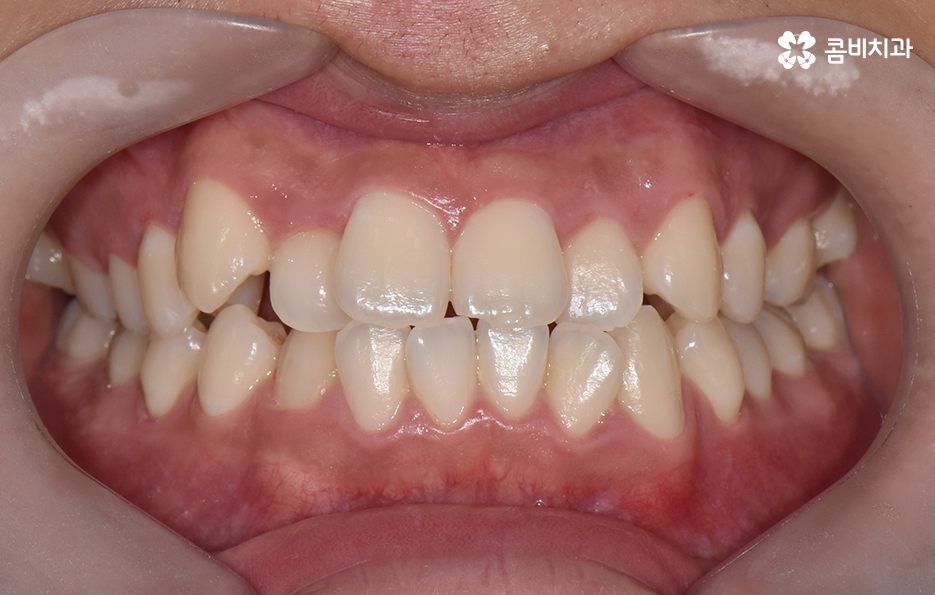

오늘 포스팅에서 보여지는 사진에서는 비발치 교정으로 덧니 교정이 가능했던 사례입니다. 덧니 교정 사례에서 발치교정 케이스는 흔한 치료 방법이긴 하지만 발치에 대한 판단은 치열만이 아니라 골격과 얼굴형을 종합적으로 고려하여 판단하고 치아를 얼마나 이동시켜야 할지 예측하여 판단하기 때문에 3D CT 등의 첨단 장비를 통한 검진과 경험 많은 교정 전문의와 충분히 상의하고 결정해야 합니다

치아교정은 치열을 가지런하게 재배열하는 치료이면서 각 개인의 얼굴형과 골격, 입술라인 등을 종합적으로 고려해야 하기 때문에 발치교정의 필요 여부를 판단하는 것에도 신중한 판단이 필요한데요

30대 치아교정 되도록 빨리 치료가 끝나길 원하시는 분들이 많겠지만 교정 치료는 결과가 중요한 치료이기 때문에 자신에게 적합한 치료 계획을 정교하게 세우는 것이 중요하며 발치는 한번 하면 되돌릴 수 없고 반대로 비발치 교정을 한다고 해도 치료상의 편의성만을 따지는 것이 아니라 결과가 중요하기 때문에 각 환자분들의 얼굴에 잘 어울리는 결과를 얻기 위해서는 비발치 교정이 얼마나 적합한지를 잘 따져봐야 하겠습니다

종합하면 발치교정의 필요성은 얼굴과의 조화, 골격 그리고 교합 등을 전체적으로 고려하여 판단하기 때문에 각 환자분들이 필요한 치아의 이동 정도를 정확히 예측하고 필요한 치아 이동 공간을 확보함에 있어서 발치교정이 적합할지 아니면 비발치적인 방법으로도 치아 이동 공간이 확보 가능한지 따져보고 있으며 발치교정이 아니더라도 치간삭제, 악궁확장, 어금니 후방이동과 같은 방법으로 공간 확보가 가능하기 때문에 각 환자분들에게 적합한 1:1 맞춤형 치료가 진행되고 있어요